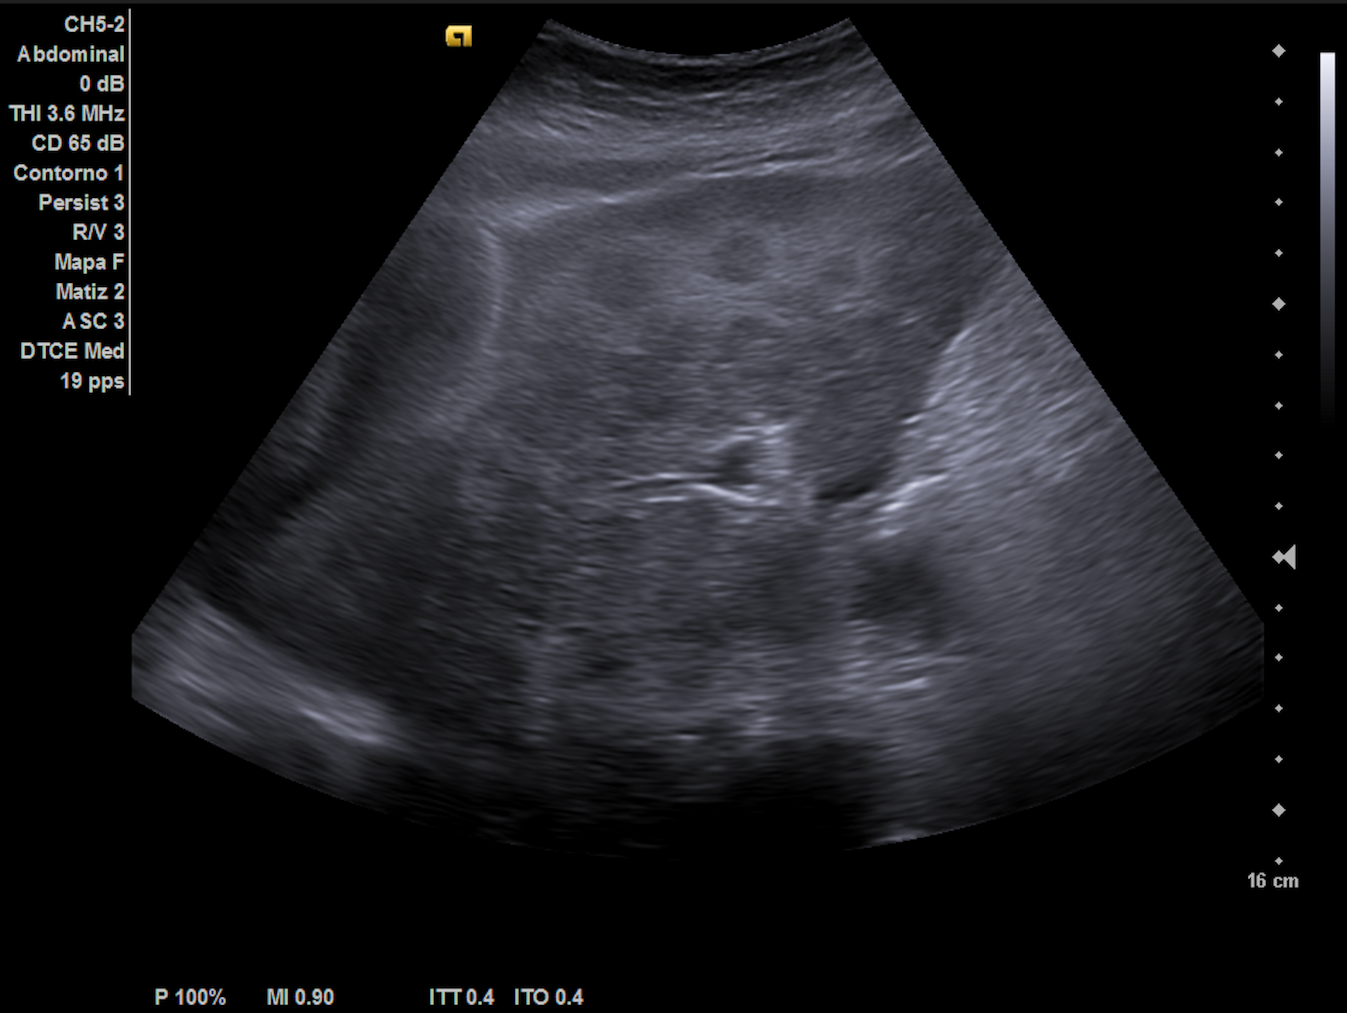

Ecografía hepática: hígado de tamaño normal con ecoestructura heterogénea, lesiones focales con halo hipoecoico en ambos lóbulos, sugerentes de metástasis. Las imágenes ecográficas del ingreso coincidían con nuestra descripción.